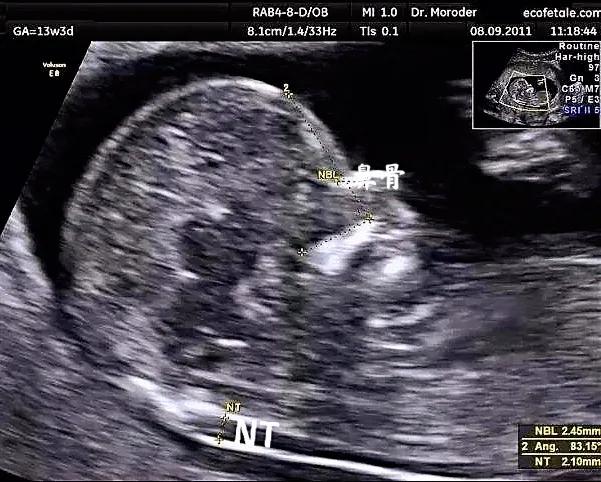

第二次超声检查

在孕11到孕13周6天之间,检查主要内容:测量NT,也就是胎儿颈后透明带。通过NT数值,结合孕妈的年龄,血清学指标,综合判断胎儿唐氏综合征的风险。除了测量NT,在这次超声时,可以大致进行胎儿一些结构的观察,如有无头颅,有无缺少一侧肢体,有无大的脐膨出等,可以更早期的排除一些严重影响胎儿的结构畸形如:无脑儿等。但是更加详细的结构观察还是要到中孕期的系统筛查,也就是俗称的大排畸。

注意事项:无需憋尿,如果胎儿姿势不合适不容易检查,可以轻轻抚摸肚子或者走动走动让胎儿调整姿势以便检查。

值得大家期待的是,在我们一妇婴检查超声,您的报告上都会有一张图2所示的宝宝的照片哦。

图2 图中箭头指的就是宝宝的NT